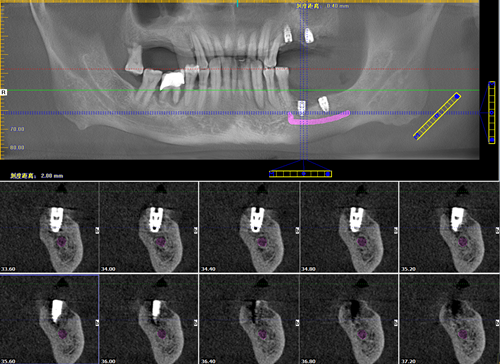

植体拥有唯一编码数字科技·精确种牙

让疑难种牙变简单

麦芽口腔的郑苍尚院长为我量身定制了"微创无痛数字化口腔种植牙"技术,种牙过程很舒适,就像被蚊子"叮"了一下牙就种好了,全程无痛,种完后也不肿不痛的,相信麦芽就是相信科学。